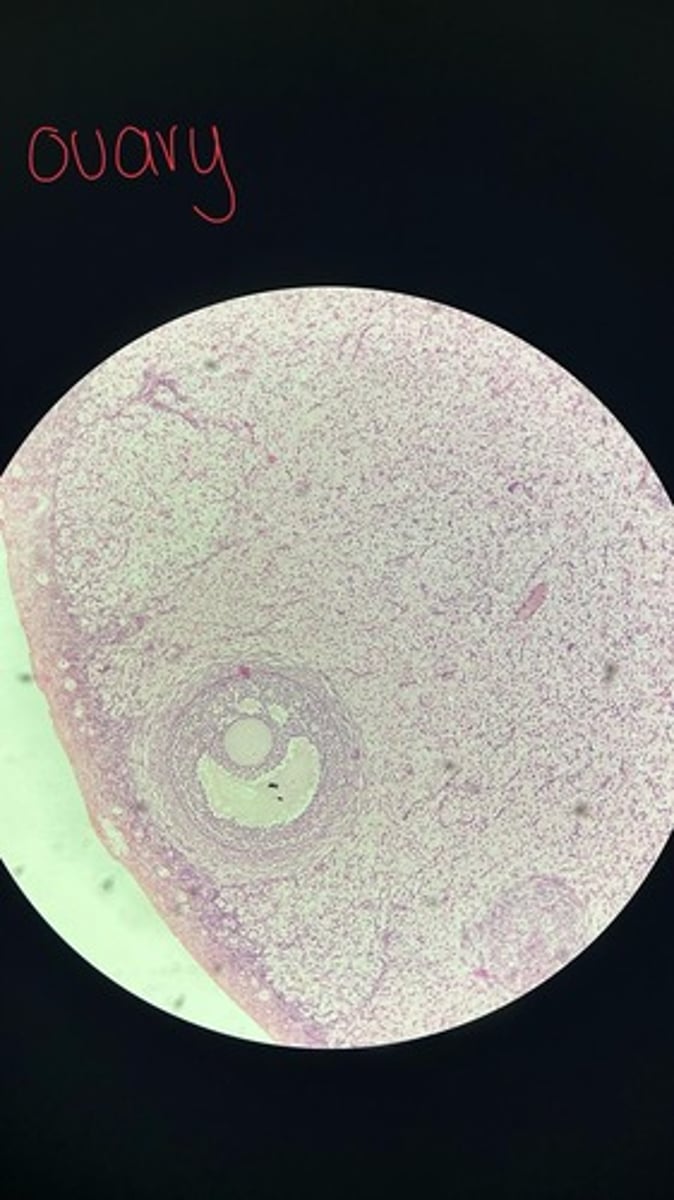

Ovary HE

Ovary HE

Ovary HE

Ovary HE

Ovary HE